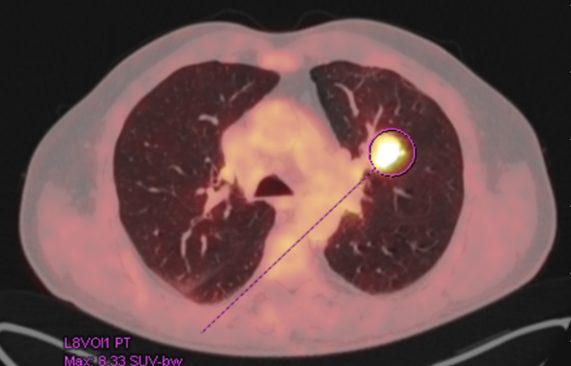

Pacient prošel multidisciplinární komisí, kde bylo onemocnění uzavřeno jak cT2 cN1 Mx s patologickou uzlinou v pánvi. Ale pro drobné plicní nodularity na bazích plic bylo doporučeno doplnit FDG PET/CT, které prokázalo patologické uzliny v pánvi a vícečetné plicní metastázy včetně ložiska v levém plicním hilu. Byla doplněna i bronchoskopie, která neprokázala bronchogenní tumor, bronchiální cytologie negativní.  V klinickém obraze se začínal rozvíjet mírný lymfedem obou dolních končetin. Dle prediktivního vyšetření TPS negativní, exprese PDL-1 méně než v 1% nádorových buněk, CPS pod 10. Celkově je pacient PS 1, občasné exacerbace CHOPN, dušnost při námaze, veden na plicní ambulanci.

Řez plicemi z CT screeningu: Stagingové PET/CT v 2/2021 potvrzuje plicní diseminaci.

Obr. 1Stagingové PET/CT v 2/2021 potvrzuje plicní diseminaci.